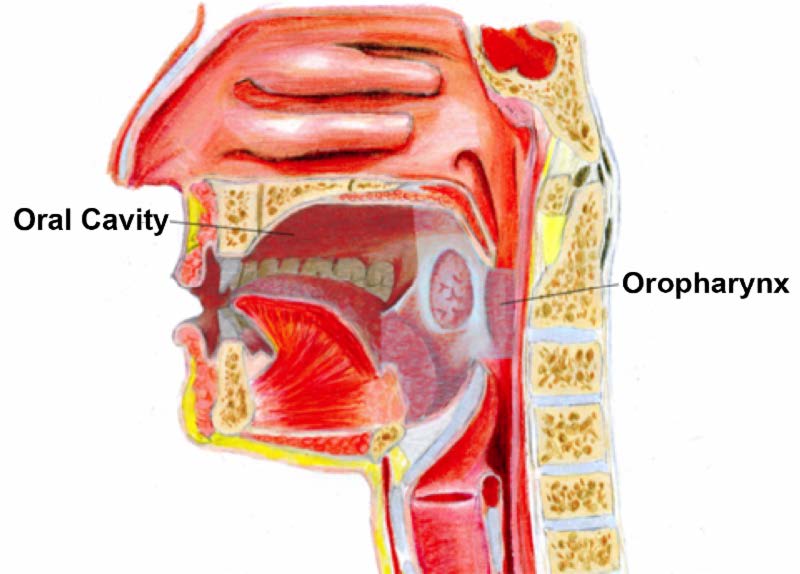

Oral Cancer Mouth Cancer Anatomy Headandneckcancerguide Org

Oral Cancer Wikipedia

Stages Of Oral Cancer Mouth Cancer Headandneckcancerguide Org

Stages Of Oral Tongue Cancer Headandneckcancerguide Org